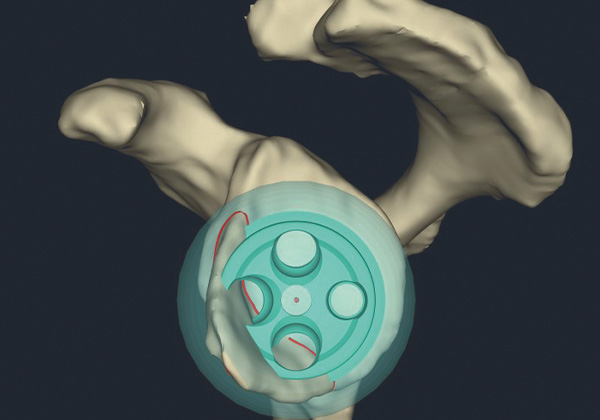

Bei diesem künstlichen Gelenk wird das Prinzip des Gelenkes „umgedreht“ - invertiert. Aus der Kugel (Oberarmkopf) wird eine Pfanne (Schulter) und aus der Pfanne wird eine Kugel. Dadurch entsteht gegenüber dem anatomischen Prinzip eine innere Führung des Gelenkes, die nicht auf die volle Funktionsfähigkeit aller vier Sehnen der sogenannten Rotatorenmanschette, die den Oberarmkopf in der Schultergelenkpfanne stabilisiert, angewiesen ist. Dieses Prinzip führt gegenüber dem anatomischen Gelenk verlässlicher zu guten Ergebnissen und es kann zudem ein weitaus breiteres Spektrum von Erkrankungen des Schultergelenks behandelt werden.

Inverse Schulterprothesen kommen bei Verschleißerkrankungen des Gelenkes, im Endstadium der Rotatorenmanschettenerkrankung (Defektarthropathie) wie auch in der Behandlung von Oberarmkopfbrüchen und in der Revisionschirurgie zum Einsatz. Ein besseres Verständnis für die Gelenkmechanik des Inversen Gelenkes führte zu Weiterentwicklungen. Neue Implantatsysteme sind durch eine höhere Modularität mit diversen Anpassungsmöglichkeiten an die anatomischen und verschleißbedingten patienteneigenen Gegebenheiten gekennzeichnet. Durch den Einsatz von digitalen dreidimensionalen Planungen, die aus präoperativen CT – Untersuchungen der Patient*innen angelegt werden, ist es möglich, diese größere Modularität auf den jeweiligen Fall individuell anzuwenden.

Fallweise kann zur besseren Umsetzung aus der Planung heraus patientenindividuell ein Instrumentarium mit Hilfe eines 3D-Druckers hergestellt werden. Dies führt zu achsengerechten Komponentenpositionen mit einer guten Beweglichkeit. Durch die optimale Zentrierung und Verringerung von Gelenkkonflikten ist zudem eine deutliche Verbesserung der Dauerhaftigkeit der künstlichen Gelenke zu erwarten.